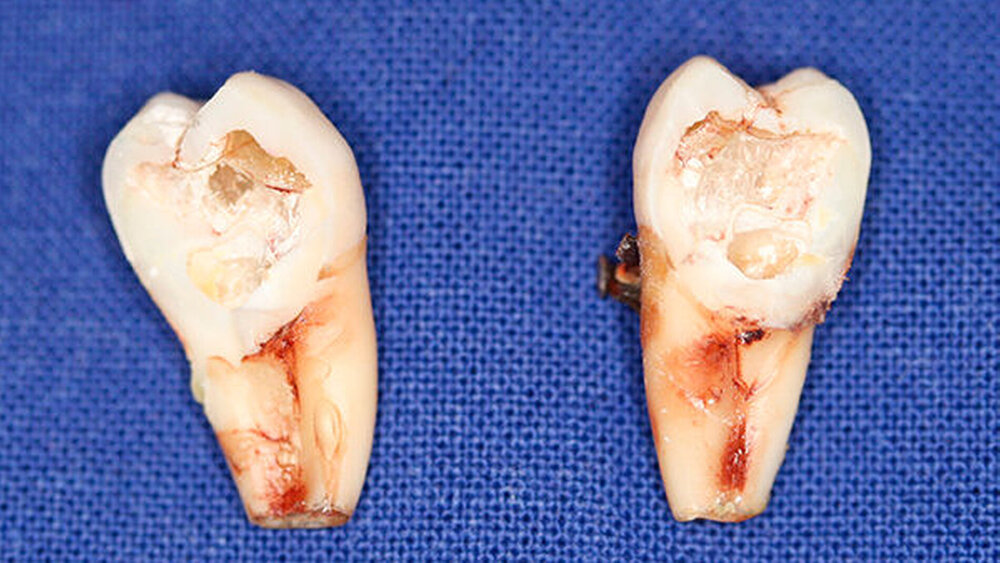

Postoperativ wurden die Zähne in bukko-lingualer Richtung mittels einer diamantbelegten Trennscheibe geteilt. Visuell zeigte sich nun ein großer Hohlraum im koronalen Dentinbereich, sowohl an Zahn 27 als auch an Zahn 47. Die histologische Untersuchung der Zahnfragmente ergab für beide Zähne: Zahnanlagengewebe mit akuter Entzündung (Abbildungen 4 bis 6). Der Patient befindet sich seitdem im regelmäßigen Abstand von sechs Monaten in einem prophylaktischen Recall. Die Abbildung 7 zeigt das postoperative Zahnschema vom 19. August 2015

Der vorliegende Fall zeigt eindrucksvoll verschiedene Stadien der präeruptiven koronalen Resorption (PIR): eine präeruptiv im Röntgenbild sichtbare Transluzenzzone im Dentin des Zahns 47 an der koronalen Schmelz-Dentin Grenze mit intaktem Schmelzmantel und eine große Kavitätenbildung nach Durchbruch des Zahns 27 in die Mundhöhle.

Bei der histologischen Untersuchung der extrahierten Zähne 27 und 47 unseres Patienten wurden Zahnanlagengewebe und Entzündungszellen gefunden. Im Rahmen anderer Untersuchungen konnten resorptive Zellen wie Osteoklasten und Makrophagen an den Rändern der Läsion nachgewiesen werden [Spierer, 2014].